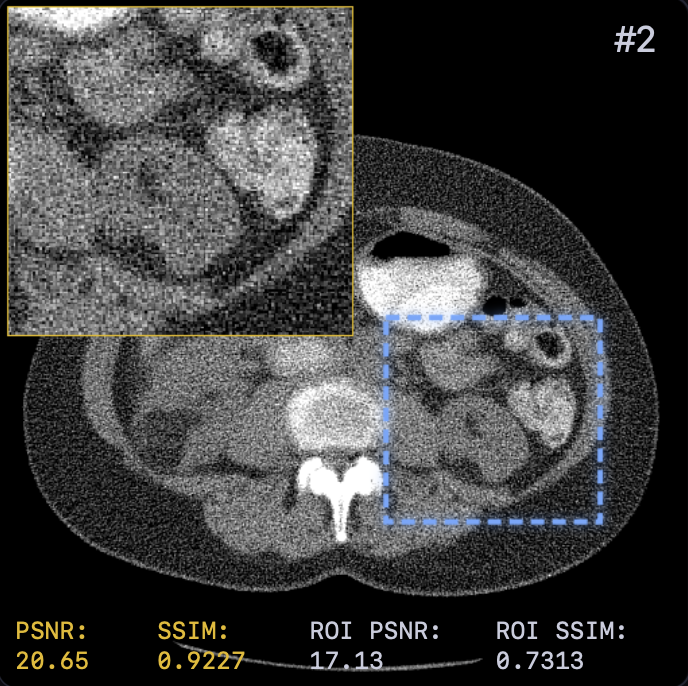

The reconstruction results are shown in Fig. 2. A zoomed-in region was extracted for a closer look with both PSNR and SSIM values attached. LTV preserves fine structures, such as vessel continuity, and reduces streak artifacts—critical for diagnostics—while avoiding the over-smoothing of TV or the anatomical inconsistencies of FBP+U-Net.